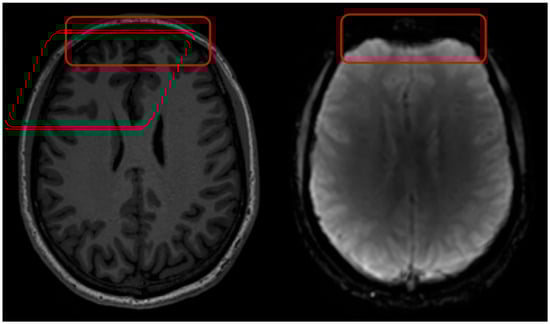

Figure 2. Geometric distortions in DSC MRI appear as misshapen or incorrectly sized brain structures, leading to spatial misregistration with anatomical images, primarily in regions near air/tissue interfaces. Geometric distortions in DSC MRI arise due to B0 field inhomogeneities and tissue susceptibility differences. On the left is a T1w MRI scan and on the right a DSC MRI scan with visible geometric distortions. The red square indicates tissue hyper intensities due to B1 field inhomogeneities.

Figure 3. B1 field inhomogeneity in DSC MRI appears as spatially varying signal intensities. The red square indicates tissue hyper intensities due to B1 field inhomogeneities.

Geometric distortions in DSC MRI result in misshapen or incorrectly sized brain structures, leading to spatial misregistration, causing the observed anatomical locations to deviate from their true anatomical positions (Figure 2). This can result in anatomic alterations observed in DSC MRI that do not correspond with the actual location of pathological tissue. Geometric distortions in EPI sequences commonly arise close to regions where the magnetic tissue properties change abruptly (like air, bone, and brain tissue), which impact the static B0 field [19,20,21,22,23]. This type of geometric distortion typically appears as deformations in the phase-encoding direction, most prominent near air–tissue interfaces such as the sinus areas in the brain. Geometric distortions can make certain areas in the brain appear in incorrect locations, have distorted shapes, or as ‘signal pile-up’ where signal from multiple voxels are displaced into a single voxel, causing localized signal increase, which complicates accurate brain mapping, diagnosis, or surgical planning.

3.3. Image Intensity Variations (B1)

B1+ field inhomogeneities refer to variations or unevenness in the distribution of the transmit radiofrequency (RF) magnetic field (Figure 3), denoted as B1+, within an MRI scanner [36]. B1 field inhomogeneity affects all MRI acquisition types, i.e., both structural T1w and EPI sequences. The B1+ field is crucial because it is responsible for flipping the spins of hydrogen nuclei in the body, enabling them to be detected by the scanner to produce an image. Ideally, this field should be spatially uniform to ensure consistent flip angles and excitation of all spins across the scanned volume, but in practice, this is often not the case.